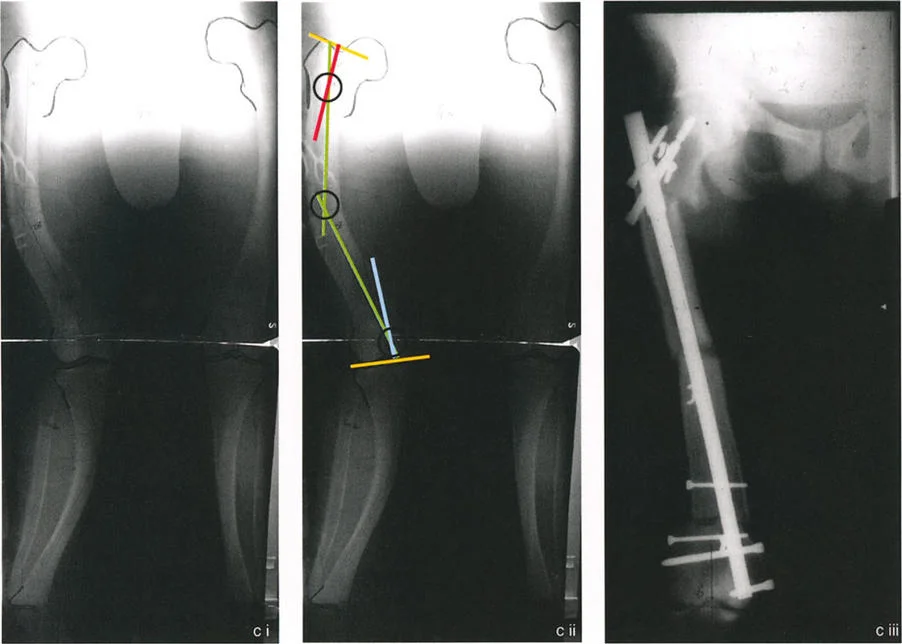

لنأخذ مثالًا لمريض شاب يُعاني من تشوه متعدد الرؤوس شديد في عظم الفخذ الأيمن بسبب الكساح، ويُعاني من انحراف في الورك (Coxa vara)، وتقوس في جسم العظم (diaphyseal varus)، وتقوس شديد في الجزء البعيد من الفخذ (distal femoral valgus).

1. تحديد القيم المرجعية: في الأمراض الثنائية (مثل الكساح)، لا يوجد طرف سليم مُقابل لاستخدامه كنموذج. لذلك، يجب استخدام الأرقام المتوسطة للسكان (mLDFA 87°، LPFA 90°).

2. رسم خطوط منتصف جسم العظم: يتم تحديد الأجزاء المستقيمة من العظم المشوه. تُرسَم خطوط منتصف جسم العظم على طول هذه الأجزاء المستقيمة. في العظم متعدد الرؤوس، سيكون لديك عدة أجزاء مستقيمة تُقاطعها انحناءات.

3. تحديد المحور التشريحي البعيد (DAA): يُرسم خط DAA بالنسبة لخط مفصل الركبة. عادةً ما يُرسم هذا الخط بزاوية 81 درجة بالنسبة لخط مفصل الركبة عند الشوكة الظنبوبية الإنسية.

4. تحديد المحور التشريحي القريب (PAA): يُرسم خط PAA بالنسبة لخط مرجعي للورك (خط من مركز رأس عظم الفخذ إلى طرف المدور الكبير). يُرسم هذا الخط بزاوية 83 درجة (aMPFA) من الحفرة الكمثرية.

5. تحديد نقاط CORA: تُنشئ تقاطعات هذه الخطوط المختلفة (منتصف جسم العظم، DAA، PAA) نقاط CORA.

• مثال على النتائج: نقطة CORA قريبة بمقدار 11 درجة (تقوس للداخل)، ونقطة CORA وسطى 34 درجة (تقوس للداخل)، ونقطة CORA بعيدة 10 درجات (تقوس للخارج).

6. تخطيط عمليات قطع العظم: تُخطط عملية تصحيح ثلاثية لقطع العظم. باستخدام تقنية FAN، يتم قطع العظم بالتسلسل، وإعادة محاذاته للمسمار النخاعي، وتثبيته. تُؤدي النتيجة النهائية إلى استعادة زاوية mLDFA بشكل مثالي إلى 85 درجة ومحور تشريحي مستقيم.

يُعد هذا التخطيط الدقيق، الذي يُجريه الأستاذ الدكتور محمد هطيف بعناية فائقة، هو مفتاح النجاح في تصحيح التشوهات الأكثر تعقيدًا، مما يضمن استعادة الوظيفة الطبيعية والمظهر الجمالي للطرف.

في مثال كلاسيكي، قد يكون حجم انحراف الورك 22 درجة. لاستعادة الطرف بالكامل، يجب إعادة محاذاة المحور الميكانيكي من خلال عمليتي قطع عظم منفصلتين: على سبيل المثال، تصحيح زاوي 22 درجة حول نقطة CORA القريبة وتصحيح زاوي 26 درجة حول نقطة CORA البعيدة. يضمن هذا النهج متعدد المستويات عودة توجيهات مفصلي الورك والركبة إلى طبيعتها، ويتم إعادة محاذاة كل من المحور التشريحي القريب (PAA) والمحور التشريحي البعيد (DAA) بشكل مثالي.